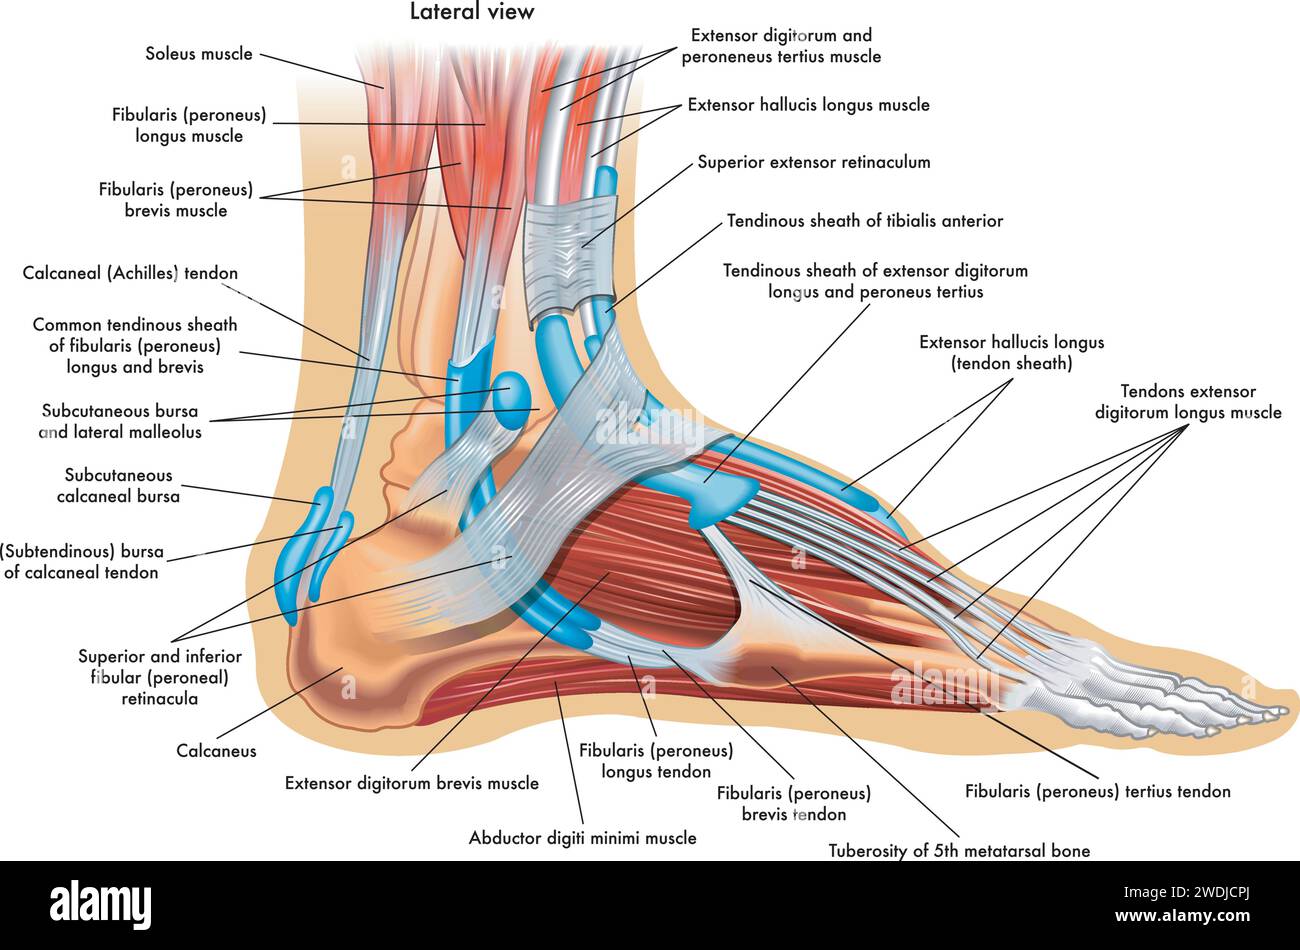

RFTCW7GT–L'articulation de la cheville, les tendons de la cheville anatomie pied eps vector illustration infographie 10

RF2X200ED–L'anatomie de l'articulation de la cheville. Région talocrurale ou os sauteur. Partie du corps humain où le pied et la jambe se rencontrent. Fascia plantaire et tendon d'Achille